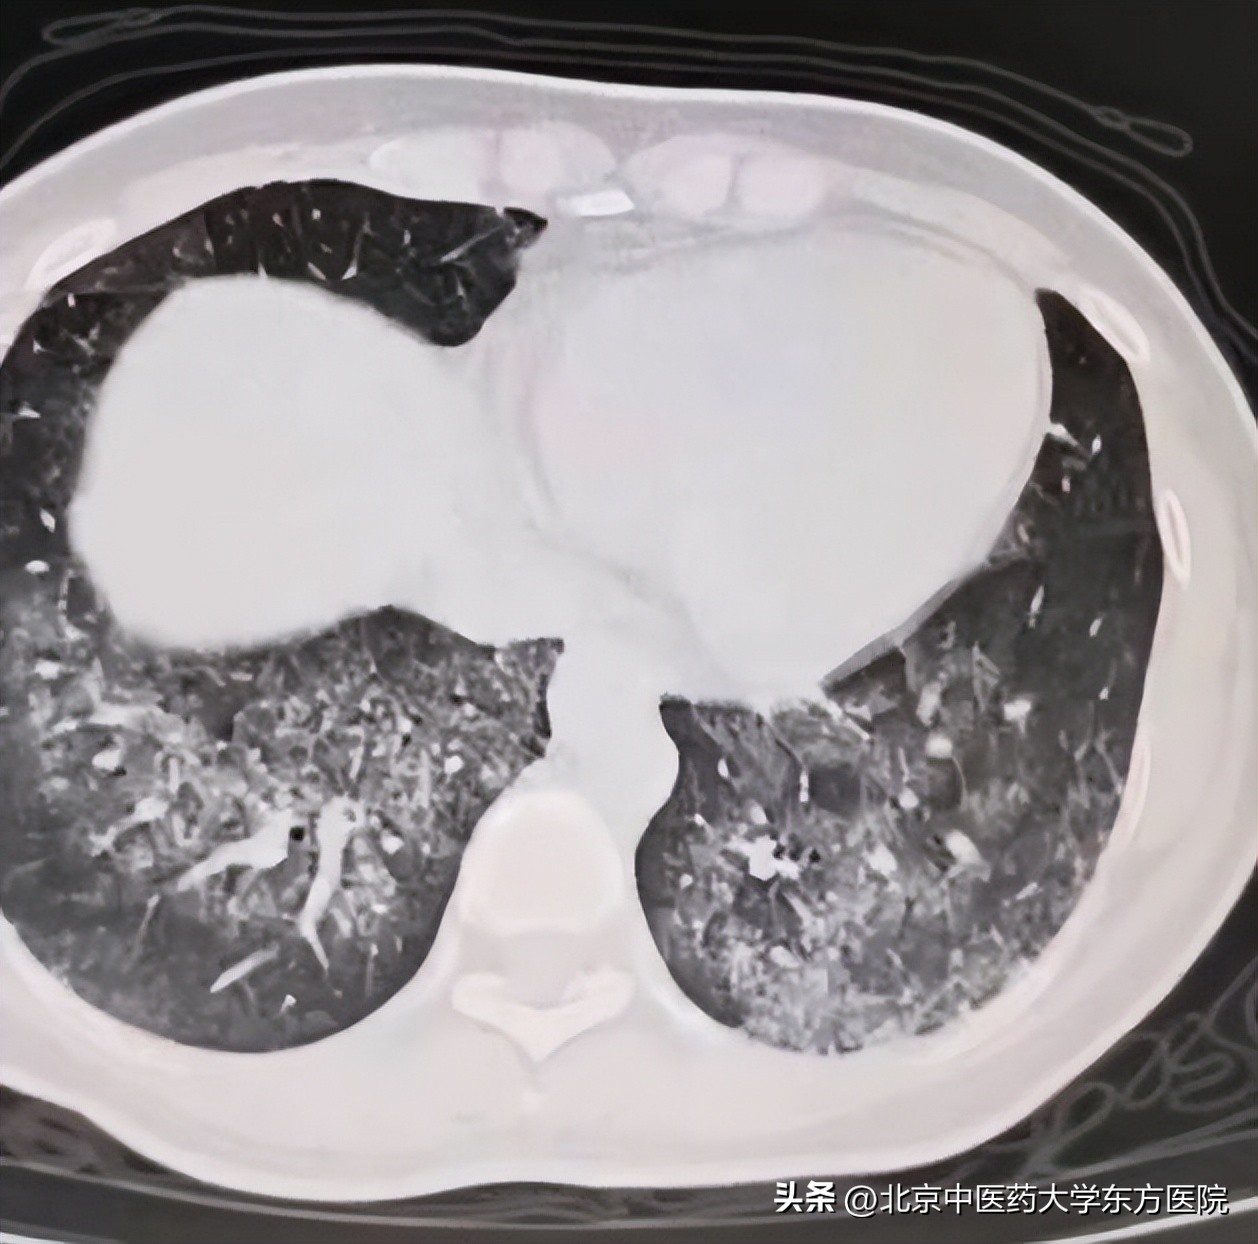

小许,33岁,因为咽痛、咳嗽、咳痰带血去看了耳鼻喉科,诊断“急性扁桃体炎”,口服抗生素几日后仍有咳嗽痰中带血,并出现活动后气短、乏力及全身多关节疼痛。她来到北京中医药大学东方医院呼吸科,查肺CT发现双肺多发斑片磨玻璃影、外周血嗜酸细胞高达27%,血色素短期下降明显(120g/L降至97g/L),这到底是怎么回事呢?

“嗜酸细胞为什么这么高?肺内弥漫分布的磨玻璃影、多关节疼痛、气短是怎么回事?”,主管医生董尚娟副主任医师面对这样一个不同寻常的病例,无数个问号出现在脑子里,肺出血?免疫病?带着这些问号完善了抗核抗体自身抗体谱、肌炎抗体谱等检查,并组织了科内线上讨论。次日呼吸科副主任马建岭当机立断为患者加急进行电子支气管镜检查,检查结果肺泡灌洗液为血性,复查血色素较入院时的97g/L下降到了81g/L,证实肺出血无误。

血性灌洗液